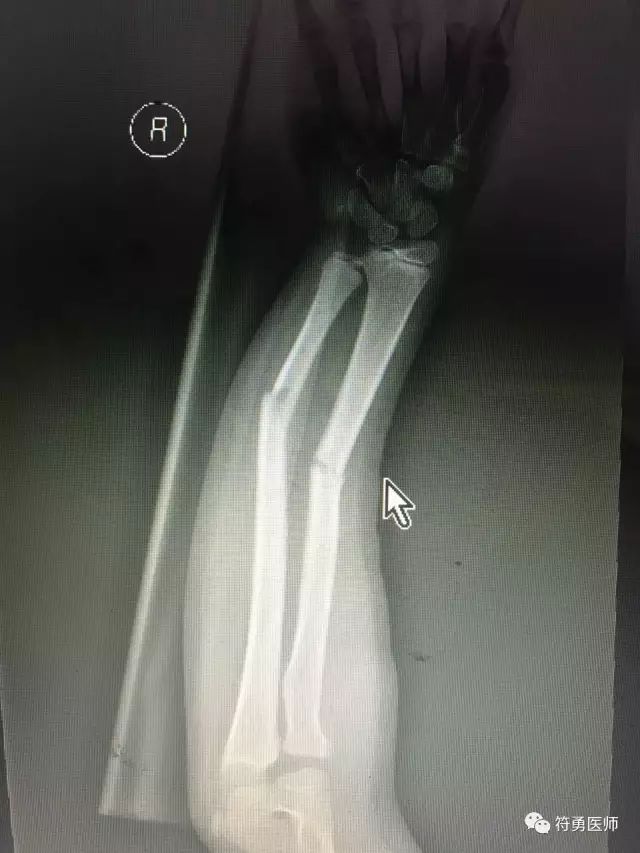

上图:摔伤后第一次找水师接骨后仍然错位,孩子受罪疼痛折腾

上图:摔伤后第一次找水师接骨后仍然错位,几乎等于没有接,孩子受罪疼痛折腾